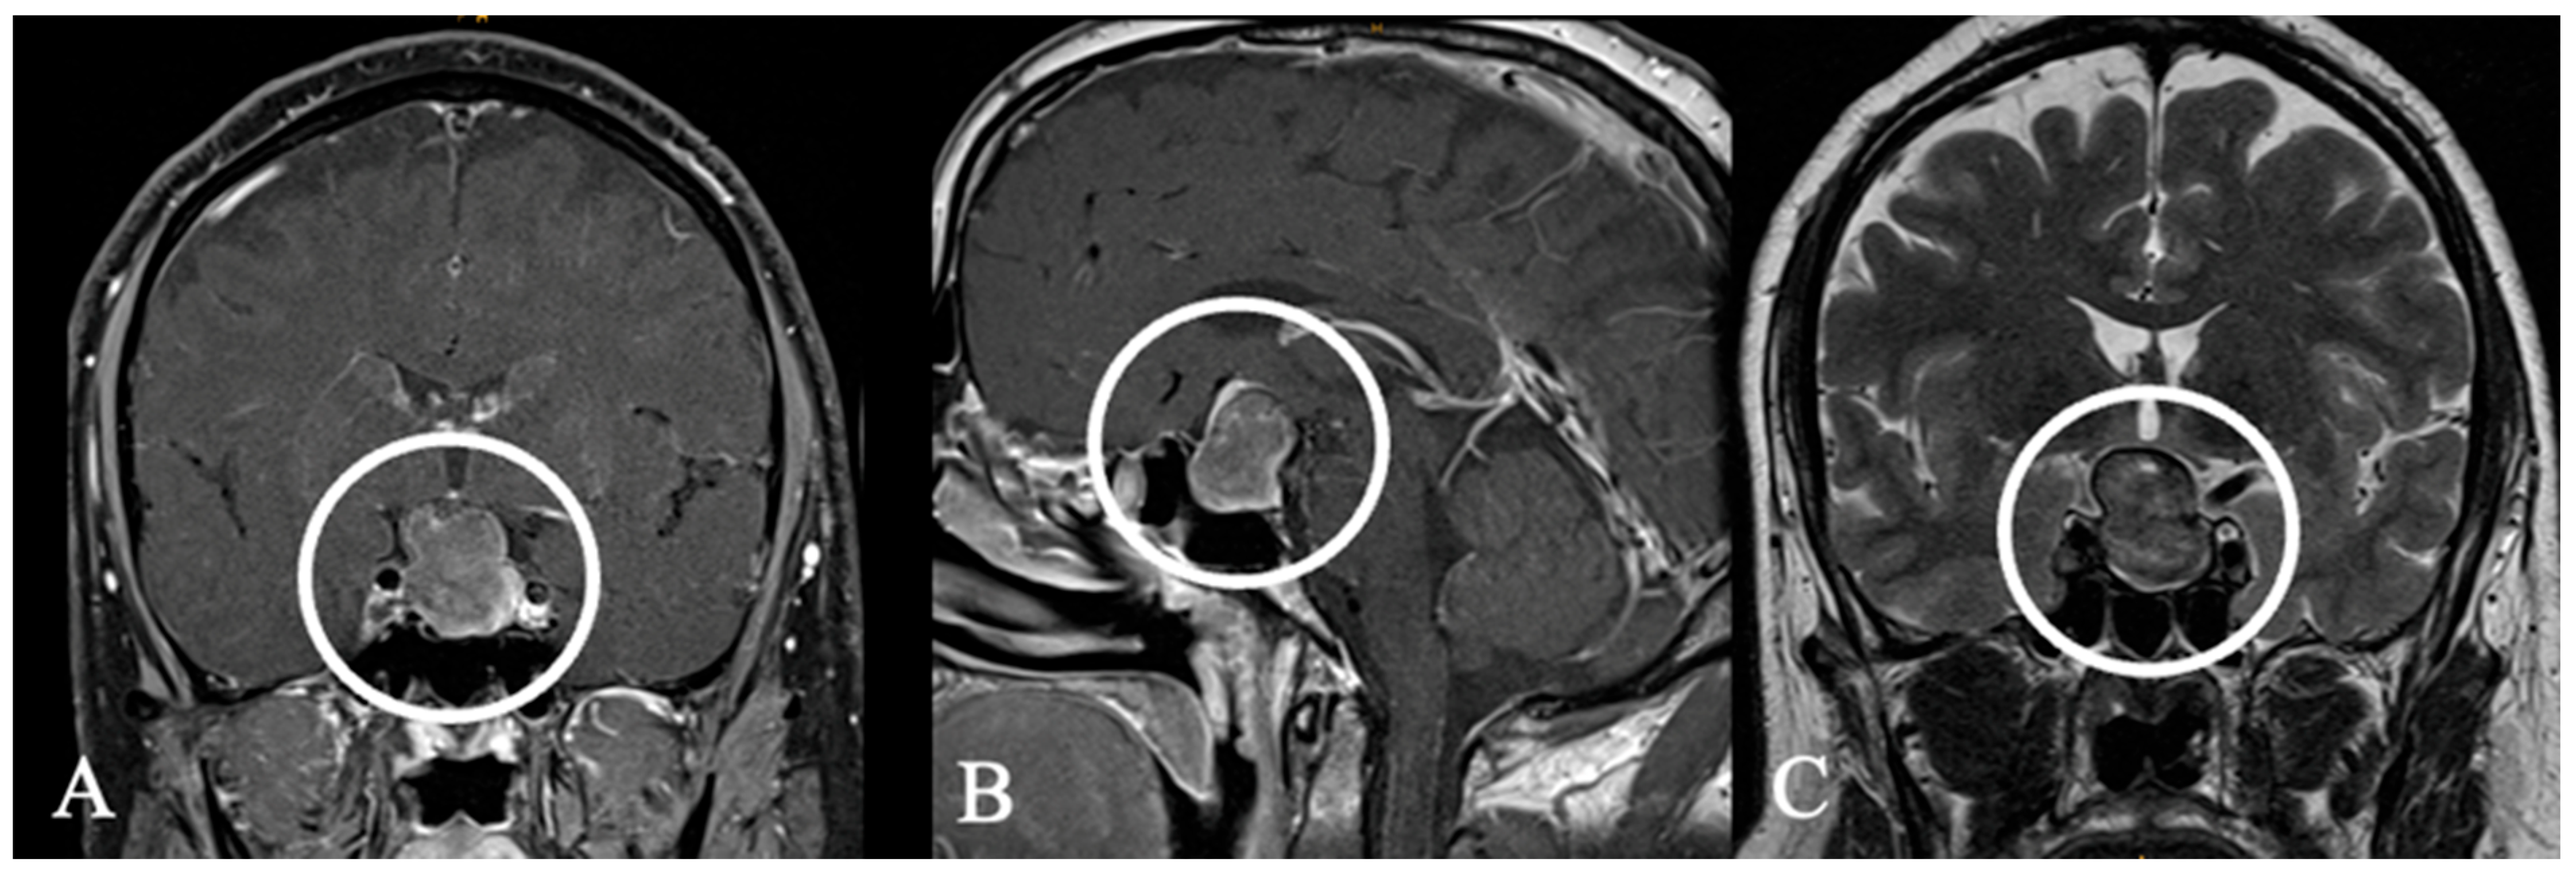

4.2. Differential Diagnoses and Case Presentations